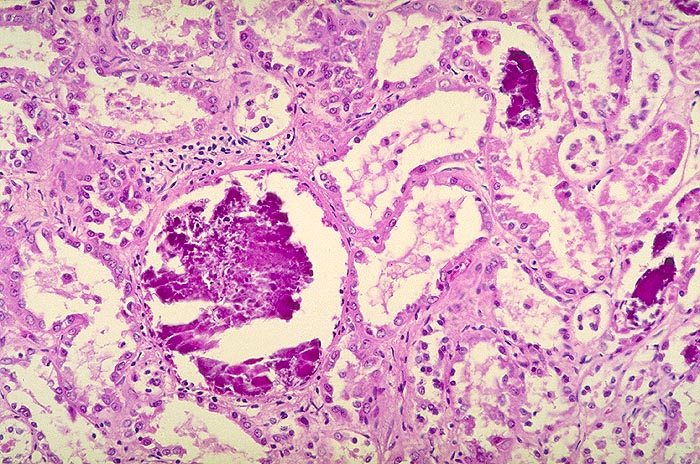

AP/ Nephrokalzinose

Nephrokalzinose

Niere